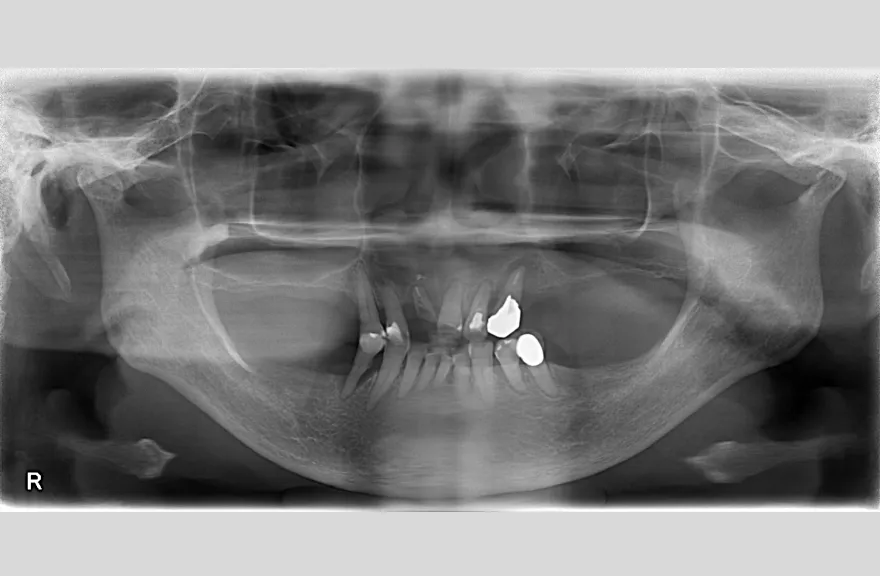

骨格の前後的な差がある方でした。術前のレントゲンより、上下で歯牙の損傷に明らかな差があるのがみてとれます。

上の歯がないところにインプラント治療を行い、上顎は全てインプラントフィクスチャーによる固定性の歯を入れられることも費用的には可能な方でした。

しかし、治療において重要なのは今目の前の歯を見ることではなく、なぜ目の前の歯になったかを考え、未来へ活かすことです。

骨格的な前後差を考慮することなく歯をいれても、装着した人工物は決して長持ちしません。

今回の症例では、敢えて上顎は総義歯形態をとり、骨格的な前後の差を解消するよう工夫しました。

上顎の残っていた歯も、差し歯としては使えずとも、敢えて根だけ残すことによって組織を温存し、義歯の安定に寄与するよう設計しました。

ここまで全体的にしっかり治療しておけば、今後の人生においてトラブルになるようなことにはならないでしょう。 - 治療のリスク

上顎の総義歯は、馬蹄形という上顎の覆う部分が小さいタイプで作成いたしました。強度に劣るため、割れる可能性があります。

下顎のクラウン・ブリッジは、丁寧な形成・印象処置と自費専門の技工士によって製作されたもので、虫歯による損傷が今後起こりにくいとは考えますが、定期的なメンテナンスは必須であり、生涯もつものではありません。

神経のない歯(失活歯)は神経がある歯に比べて力が大きくかかりやすく、根が割れたりするリスクがあります。割れ方にもよりますが、基本的には歯が割れてしまうと抜歯処置を行わなければならないことがほとんどです。